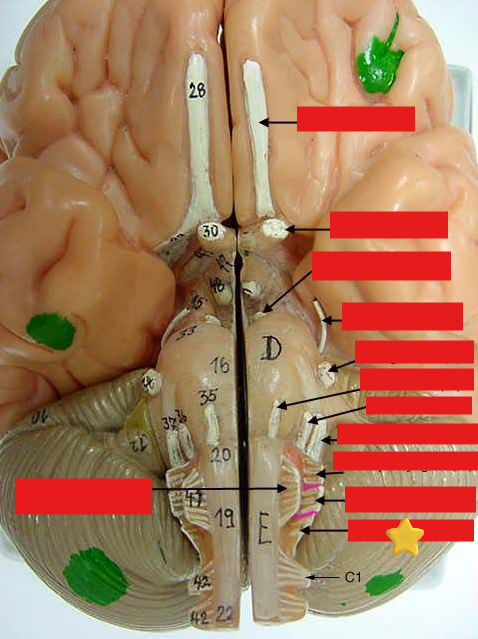

cranial nerves

12 Terms

1

olfactory

2

optic

3

oculomotor

4

trochlear

5

trigeminal

6

abucens

New cards

7

facial

8

vestibulocochlear

New cards

9

glossopharyngeal

New cards

10

vagus

New cards

11

accessory

New cards

12

hypoglossal

New cards